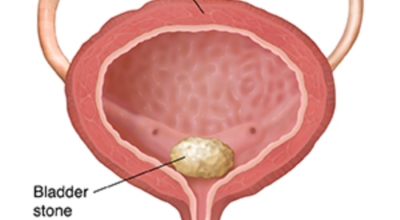

요로결석 증상 - 배뇨 이상 또는 배뇨통

방광 결석, 요도 결석은 소변 볼 때 심한 통증과 소변을 빈번히 보거나 잔뇨감 과 같은 증상이 나타날 수 있답니다. 요도 결석인 경우 심한 통증과 소변을 보지 못해 응급실을 가는 경우도 있습니다.